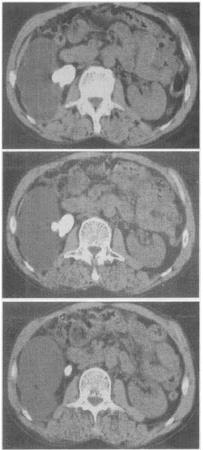

患者,女。48岁。反复血尿伴右侧腰痛7个月。CT扫描图像见图。最有可能的诊断是()。

A、肾囊肿

B、肾结核

C、多囊肾

D、肾脓肿

E、肾结石

E